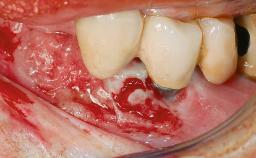

Biological complications caused by undetected cement residue have been receiving much attention. Excess cement might be responsible not only for rapidly developing of peri-implantitis, but also for delayed or chronic manifestations of the disease many years after cementation (Wilson 2009; Linkevicius and coworkers 2013). Invitro and clinical studies have shown that it is very difficult or even impossible to completely clean up excess cement at subgingival margins, so popular in cemented restorations (Agar and coworkers 1997; Linkevicius and coworkers 2011, 2012). Possible outcomes of biological complications due to excess cement range from temporary inflammation of the peri-implant soft tissues without any serious esthetic and functional consequences all the way to implant loss. This report describes a case of peri-implantitis caused by residual cement; as well as the management and quite unusual resolution of the complication. The patient presented in 2009 with a draining sinus tract, tenderness on chewing, and tissue contact above the implant-supported restoration. The implant had been restored approximately three years before.